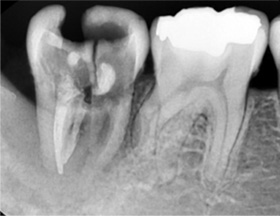

1년전 다른 치과에서 보철치료를 받은 부위에 지속적인 통증과 잇몸 염증으로 내원, 기존 보철물 수복시 신경관을 제대로 치료하지 못하여 염증이

재발된 상황이었습니다. 고운미소에서는 기존 포스트를 제거하고 오염된 부위에 약재를 삽입하여 염증을 제거하는 신경치료를 시행하였습니다.

지속적인 통증과 잇몸염증